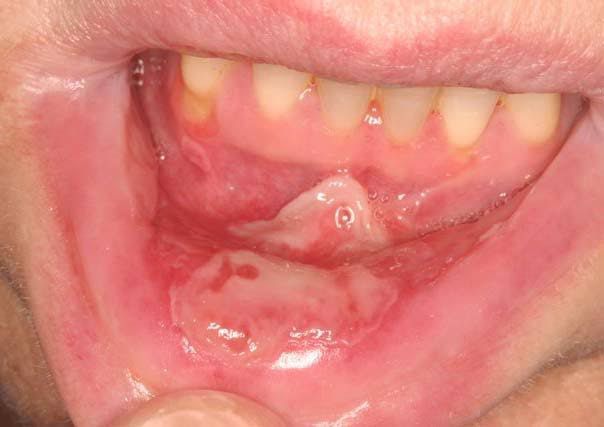

Mucositis is inflammation of the mucous membranes in the mouth and other parts of the body. Symptoms include: Mouth sores: Painful ulcers or blisters in the mouth Pain: Pain in the mouth, throat, or gums Difficulty swallowing: Painful swallowing or difficulty swallowing Dry mouth: Dry mouth or lips Bad breath: Bad breath White or red patches: White or red patches in the mouth Thick saliva: Thick and sticky saliva Bleeding: Bleeding from the gums or bottom Diarrhea: Frequent, watery stools Loss of appetite: Loss of appetite Fatigue: Fatigue